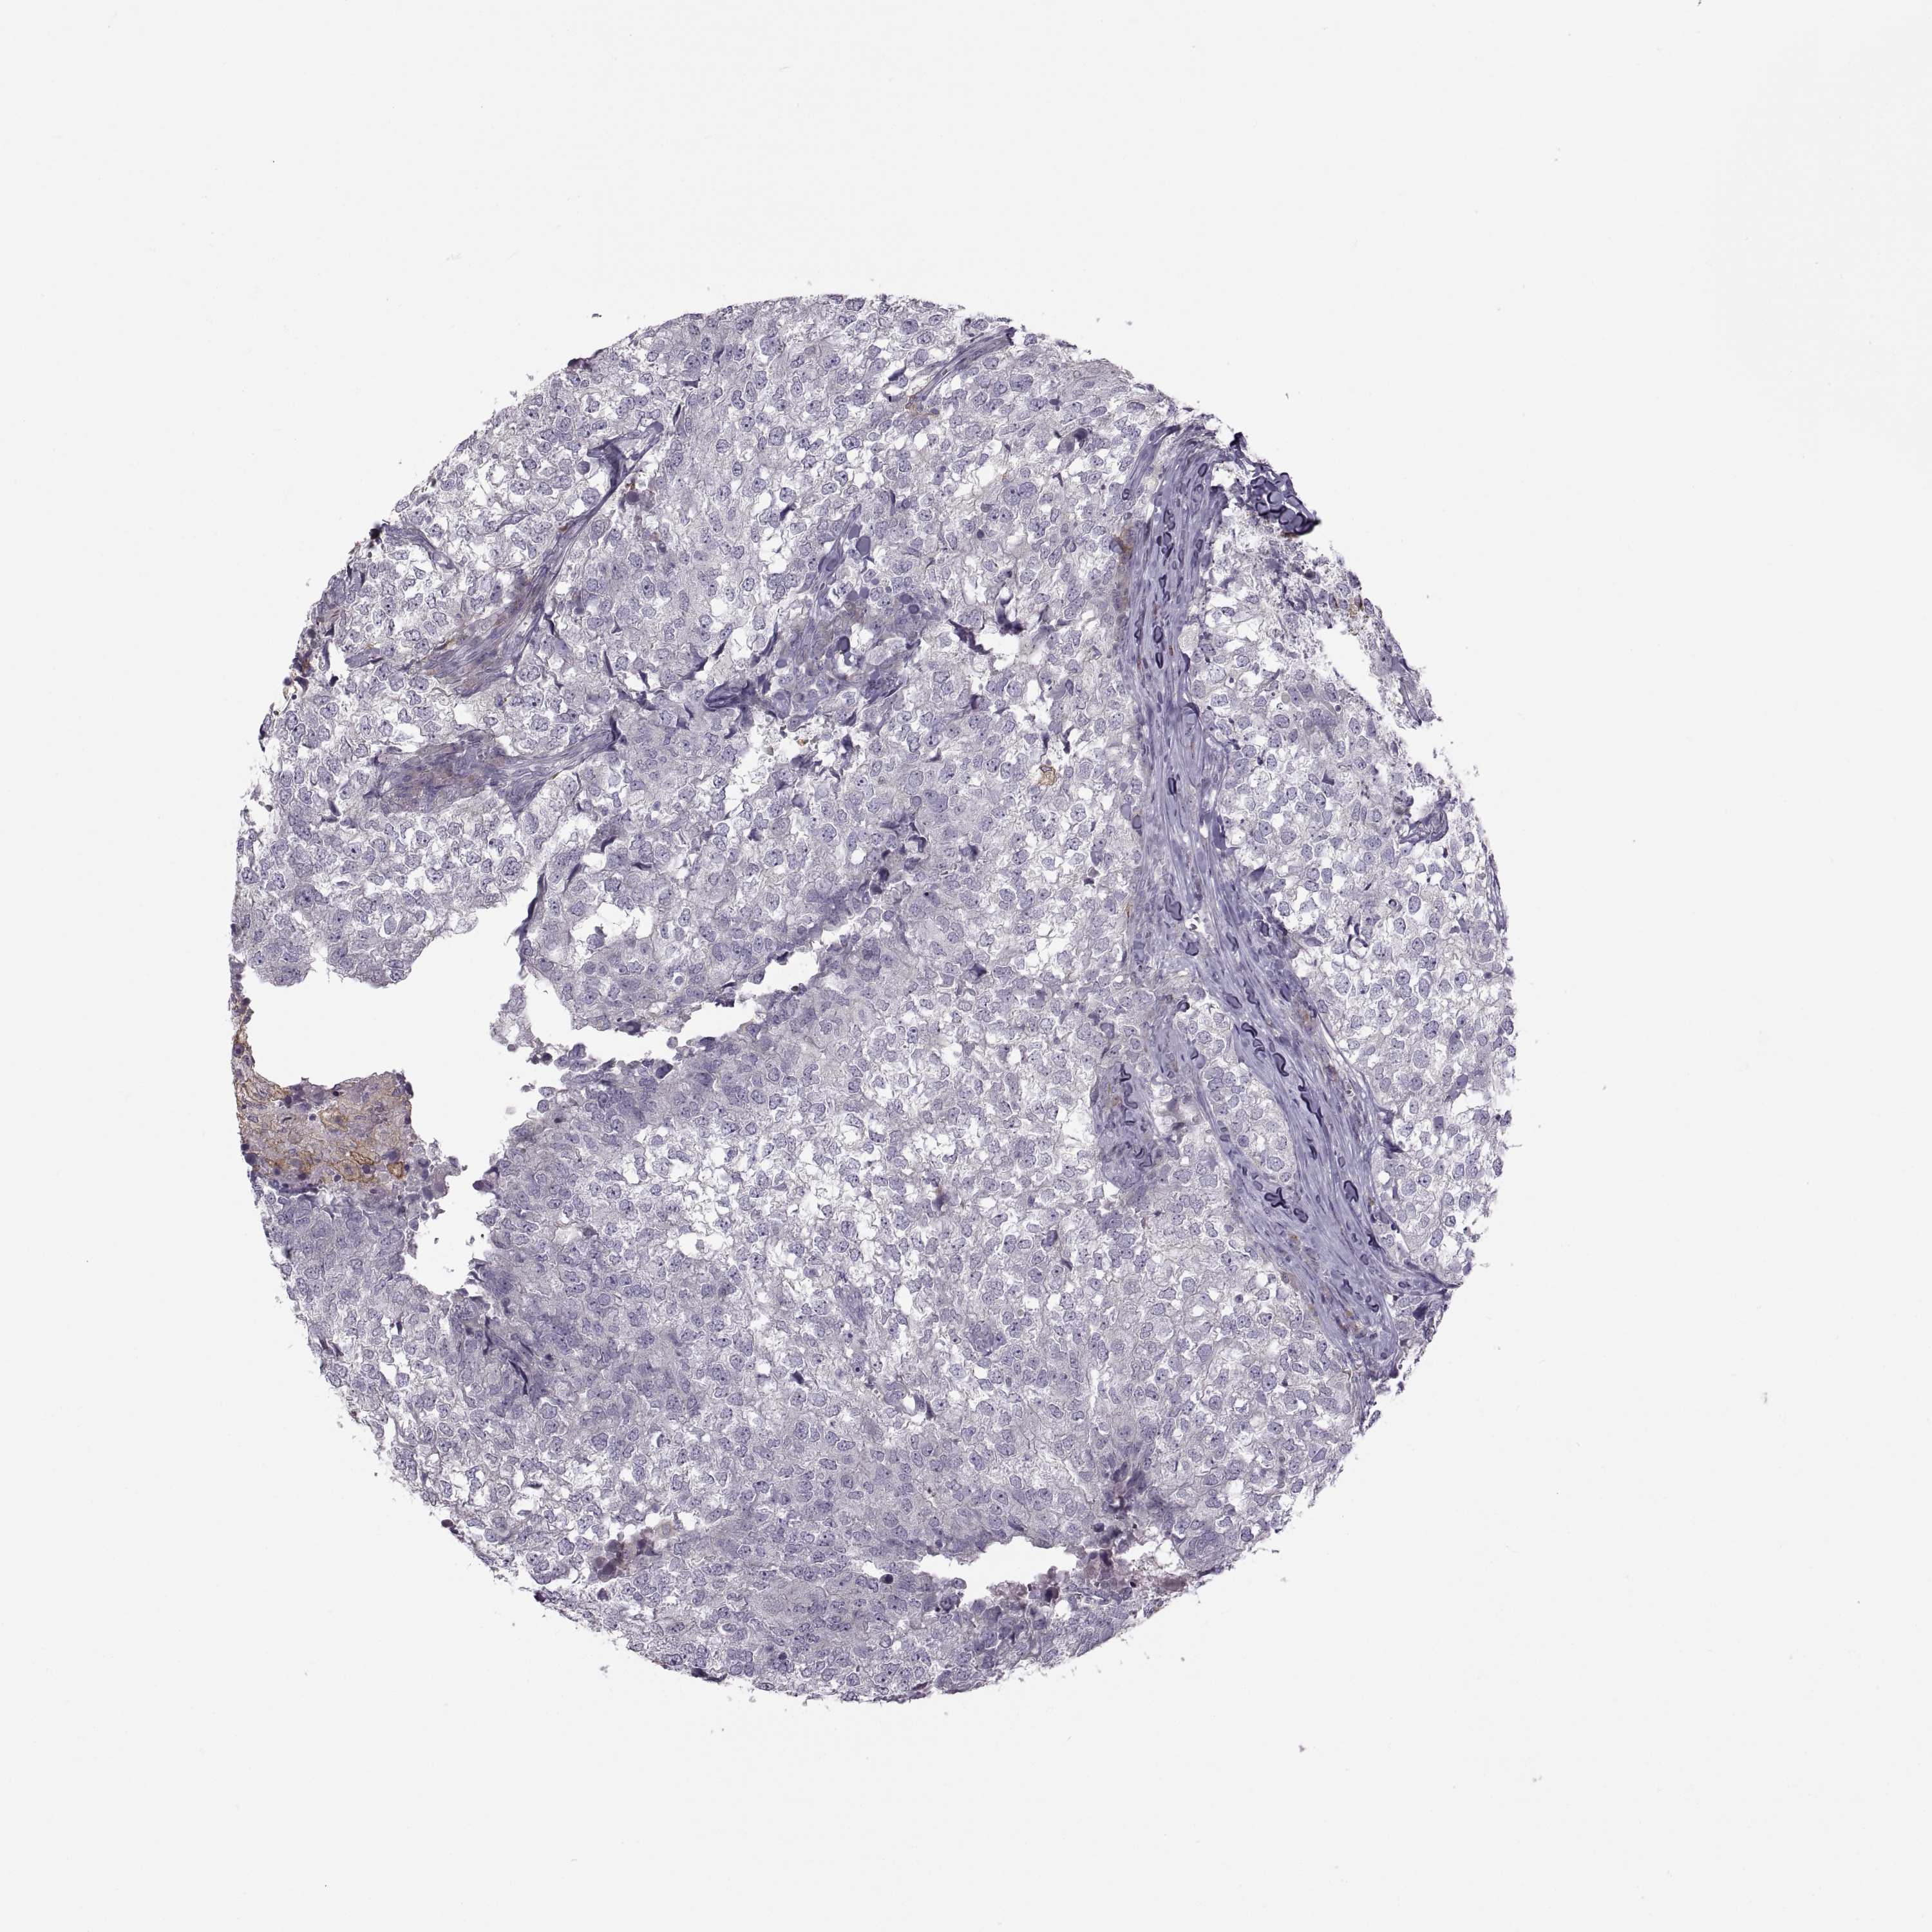

CANCER BREAST CANCER Show tissue menu

BRCA TCGA BRCA VALIDATION PROTEIN EXPRESSION